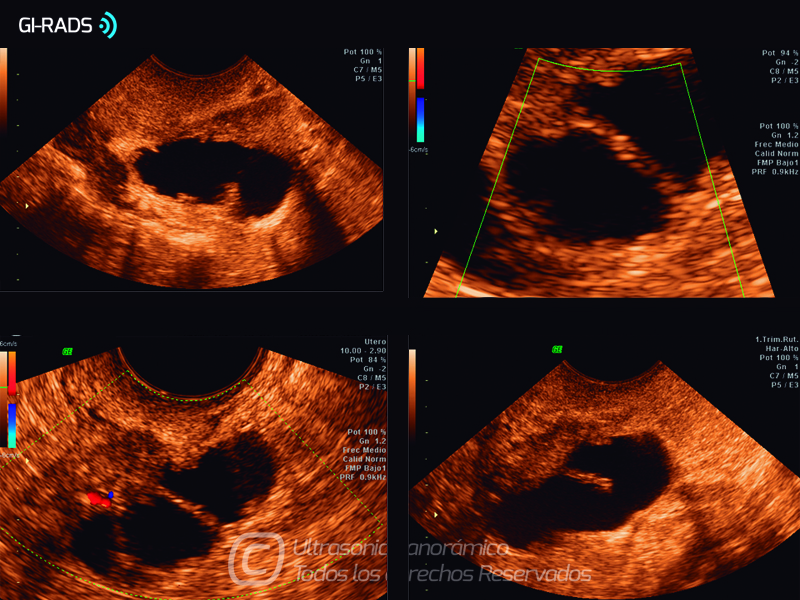

Patologías Benignas – Hidrosalpinx